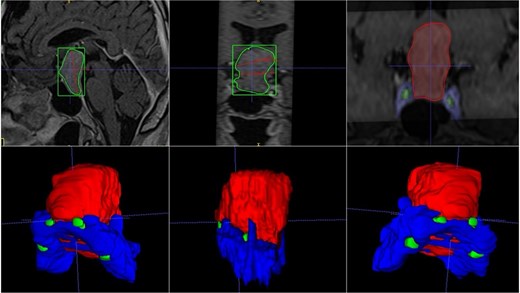

A 68-year-old male patient with an 8-year history of gradual loss of visual acuity. An MRI study was performed with the following sequences: T1, T2, and T1 with contrast. When performing the three-dimensional segmentation, we realized the intimate relationship that the dorsum of the tumor had with the basilar artery; its dolichoectatic course on the dorsal surface of the tumor was what we paid the most attention to and what made us plan a better transnasal approach and avoid the traction of the capsule mainly the dorsal region (Fig. 6).

(A, B and C) MRI of pituitary marcoadenoma in coronal, axial and sagittal sections, contrasted T1, T2, and T1 sequences. (D and E) Planimetric segmentation with 3D reconstruction of the basilar and carotid system. White arrow, relationship of the dorsum of the tumor with the basilar artery.